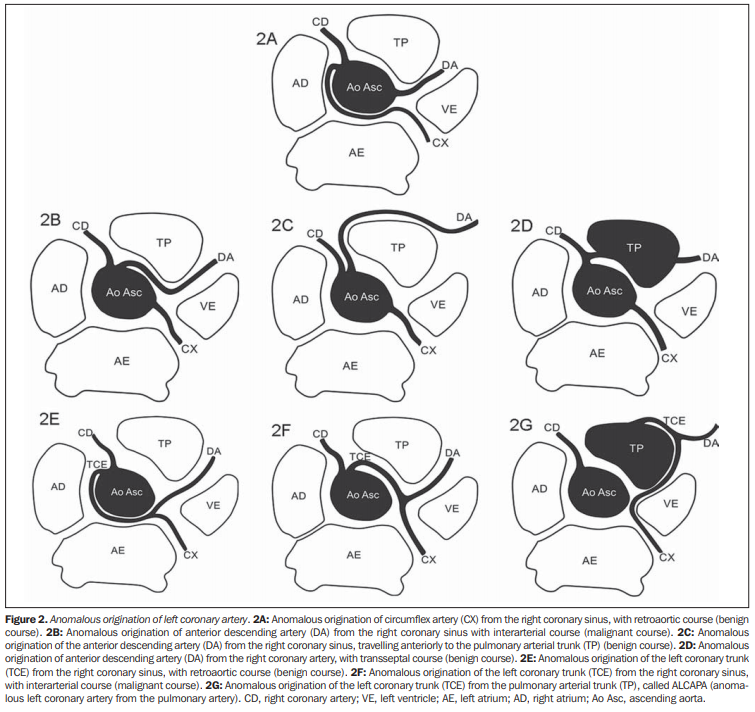

Anomalie de naissance de la CG

- Trajet Malin = Si une branche circule entre l’aorte et le tronc pulmonaire (trajet interartériel)

- Naissance de l’IVA à la CD avec trajet inter-artériel (2B)

- Naissance du TC de la CD avec trajet inter-artériel (2F)